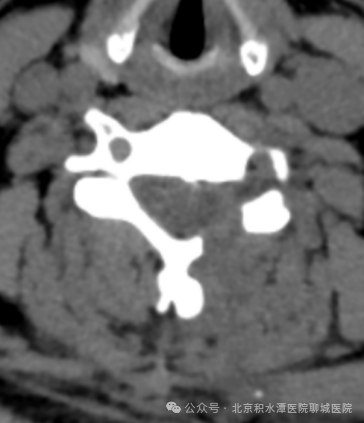

术前影像:C5/6椎间盘向左后方突出,压迫神经根

术后影像:去除C5/6左侧椎管背侧少量骨质

进行减压并摘除突出的间盘组织